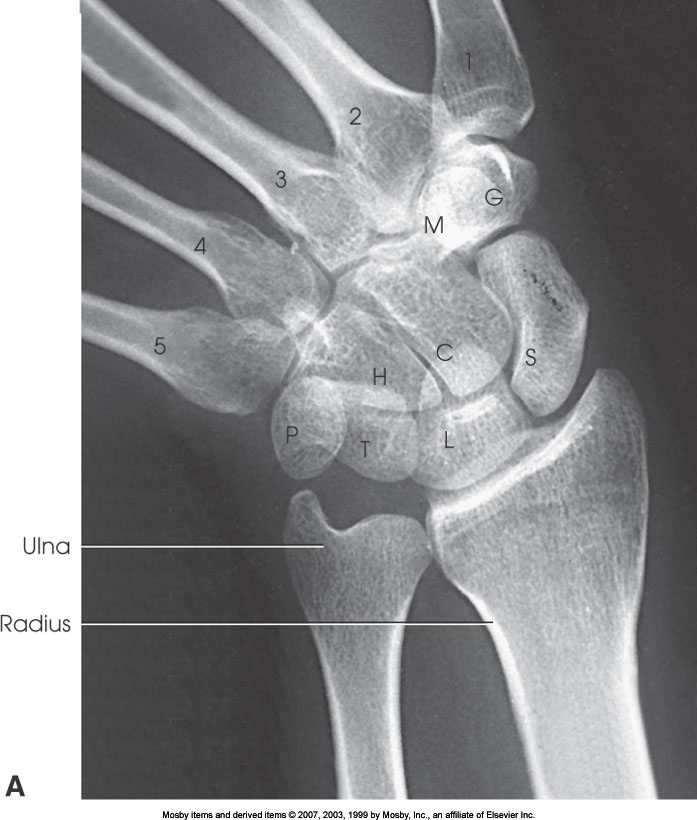

What position is demonstrated?

Lateral Wrist